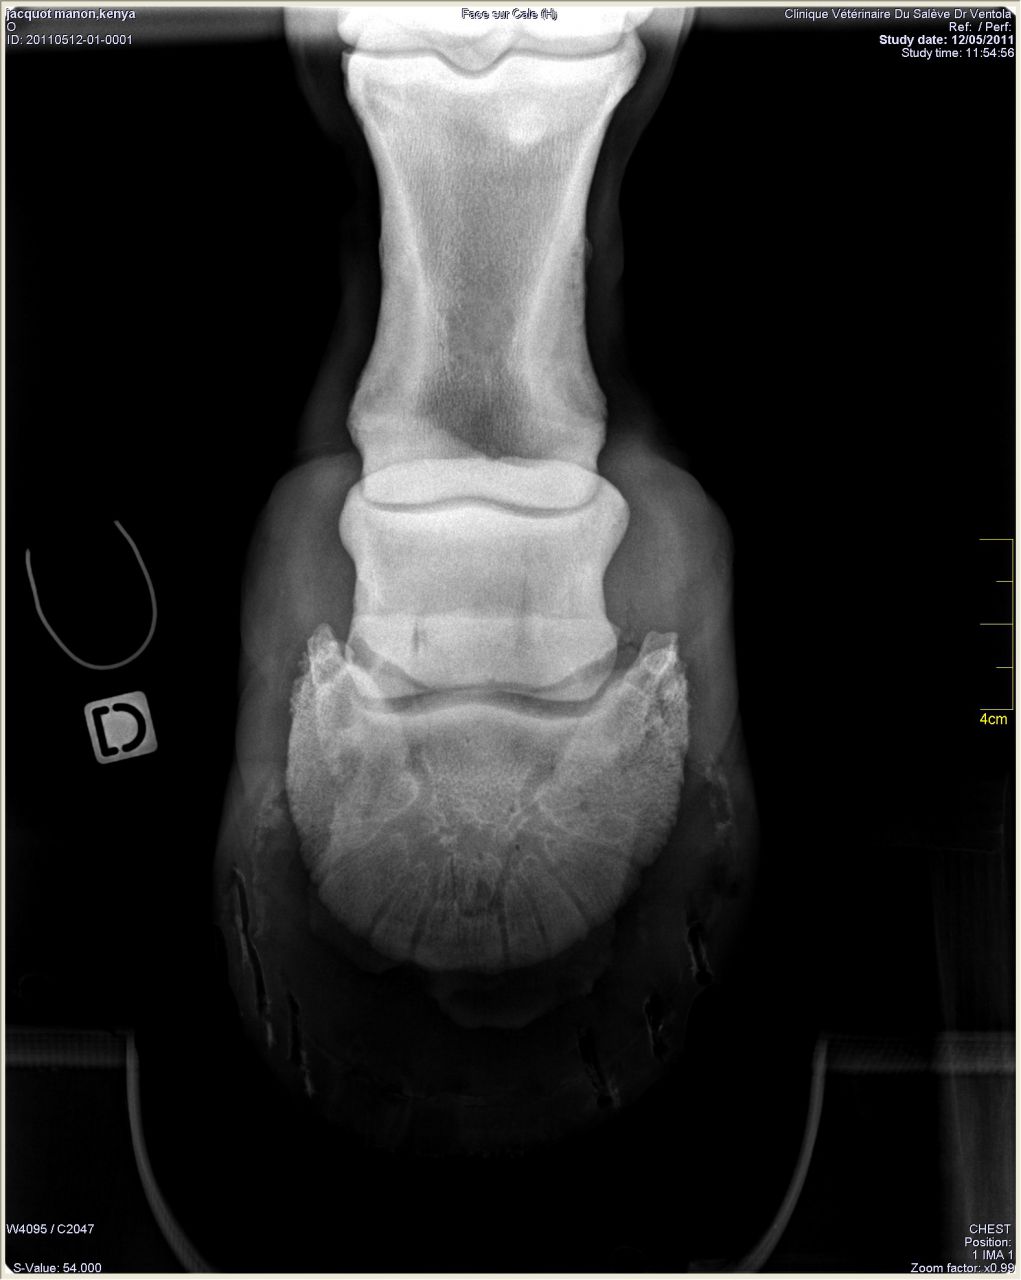

| Dire merci | Donc les radios: Antérieur gauche de profil où on peut voir le petit bout d'os au somment entre les phalanges 2 et 3 ![]() On peut noter un autre souci: normalement le milieu de la 2ème phalange doit être aligner avec le milieu du pied (c'est ce que représente le trait vertical marqué 77mm). Or ici le pied est à 2/3 devant. Ce qui a un effet levier et fatigue donc les tendons de la jument. Le pied gauche de face à plat: ![]() On peut remarquer que la 1ère phalange n'est pas nette (le véto m'a dit qu'on dirait une radio d'un cheval de 20ans.... :/) Le pied gauche de face en extension: ![]() |

Par Manon74 : le 13/05/11 à 13:43:06

| Dire merci | Antérieur droit de profil: RAS à part le même problème de répartition du pied![]() De face à plat: ![]() De face en extension: ![]() |